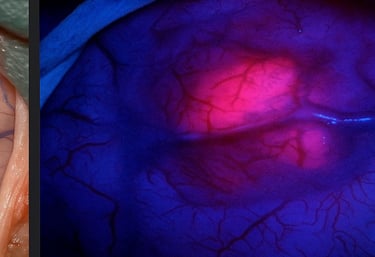

Fluorescence-Guided Surgery

(5-ALA)

A targeted dye that illuminates tumor cells under blue light, helping distinguish tumor from normal brain tissue.